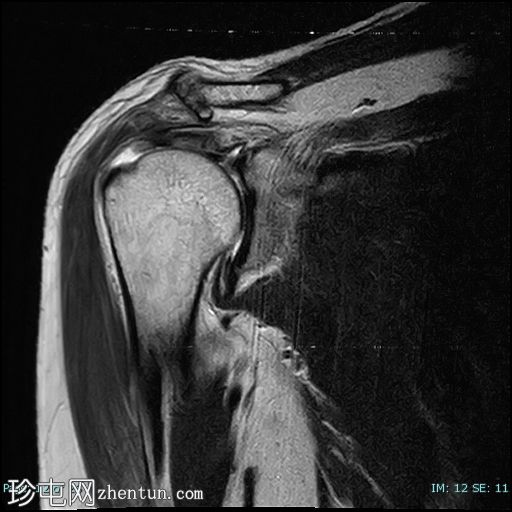

轴位PD

脂肪抑制

冈上肌腱前部纤维及肌腱止点-关键区交界处全层撕裂。撕裂间隙被T2/PD高信号液体填充。肌腱回缩2.1厘米,位于肩峰水平。

未见肱骨头骨内囊性改变或冈上肌腱神经节/黏液囊肿。

冈上肌腱变薄并伴有肌腱病,冈上肌脂肪变性为2级(Goutallier分级)。

本病例展示了退行性冈上肌腱撕裂的典型位置,即肌腱足印和关键区交界处。这与创伤性撕裂(通常发生在肌腱交界处)形成对比。

应注意,不应过度依赖质子密度加权成像序列来诊断肩袖撕裂,因为该序列容易出现魔角伪影,从而模拟撕裂。较长的回波时间序列(例如T2加权成像)可以有效避免这种假阳性结果。